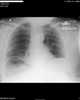

Chilaiditi syndrome is a rare condition when pain occurs due to transposition of a loop of large intestine (usually transverse colon) in between the diaphragm and the liver, visible on plain abdominal X-ray or chest X-ray.Normally this causes no symptoms, and this is called Chilaiditi's sign. The sign can be permanently present, or sporadically. [Source: Wikipedia ]

Interposition of colon between liver and right hemidiaphragm

Abnormal right upper quadrant abdominal gas collection

Unilaterally elevated diaphragm